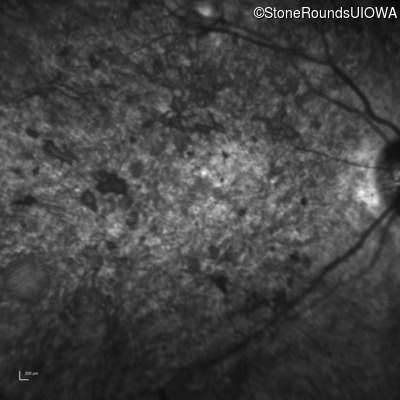

Infrared Fundus Photograph - Left - 20/250 sc

Exemplar